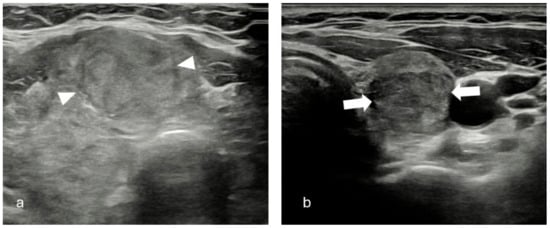

| Size | Composition | Echogenicity | Shape | Margin | Echogenic Foci | TIRADS System | |||

|---|---|---|---|---|---|---|---|---|---|

| ACR | EU | K | |||||||

| 1 | 13 mm | Solid | Hyperechoic | W > T | Smooth | Microcal. | 4 q | 5 | 4 |

| 2 | 12 mm | Solid | Hyperechoic | W > T | Smooth | Microcal. | 4 q | 5 | 4 |

| 3 | 13 mm | Solid | Hypoechoic | W > T | Smooth | None | 4 q | 4 q | 4 |

| 4 | 14 mm | Solid | Hyperechoic | T > W | Smooth | None | 4 q | 5 | 4 |

| 5 | 24 mm | Solid | Hyperechoic | W > T | Smooth | None | 3 q | 3 | 3 |

| 6 | 14 mm | Solid | Hyperechoic | W > T | Smooth | Microcal. | 4 q | 5 | 4 |

| 7 | 17 mm | Solid | Hyperechoic | W > T | Smooth | Rim | 4 | 3 q | 3 q |

| 8 | 12 mm | Solid | Hypoechoic | W > T | Smooth | None | 4 q | 4 q | 4 |

| 9 | 15 mm | Solid | Hyperechoic | W > T | Smooth | None | 3 q | 3 q | 3 q |

| 10 | 18 mm | Solid | Hyperechoic | W > T | Smooth | None | 3 q | 3 q | 3 q |

| 11 | 14 mm | Solid | Hypoechoic | W > T | Irregular | None | 4 q | 5 | 5 |

| 12 | 12 mm | Solid | Hyperechoic | W > T | Smooth | Microcal. | 4 q | 5 | 4 |